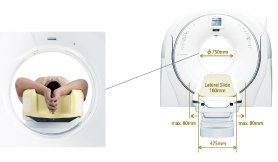

Улучшение пространственного разрешения даже при перемещении стола вбок.SCENARIA оснащена механизмом бокового смещения стола, который позволяет увеличить подвижность стола в поперечной плоскости. Предполагается, что пространственное разрешение должно улучшаться за счет размещения исследуемой области в центре гентри.

Открытый дизайн

Достаточно широкая апертура гентри — 750 ммАпертура диаметром свыше стандартных 50 см крайне удобна не только для исследования тучных пациентов, но и для исследования пожилых людей, которым тяжело закидывать руки за голову.

Широкий стол

Широкий стол шириной 475 мм и продуманный специалистами Hitachi до каждой мелочи: матрас с боковыми отворотами позволяют удобно расположить пациента и обернуть его на время исследования. Отвороты матраса также предотвращают попадание капель контраста или крови на движущиеся части стола.